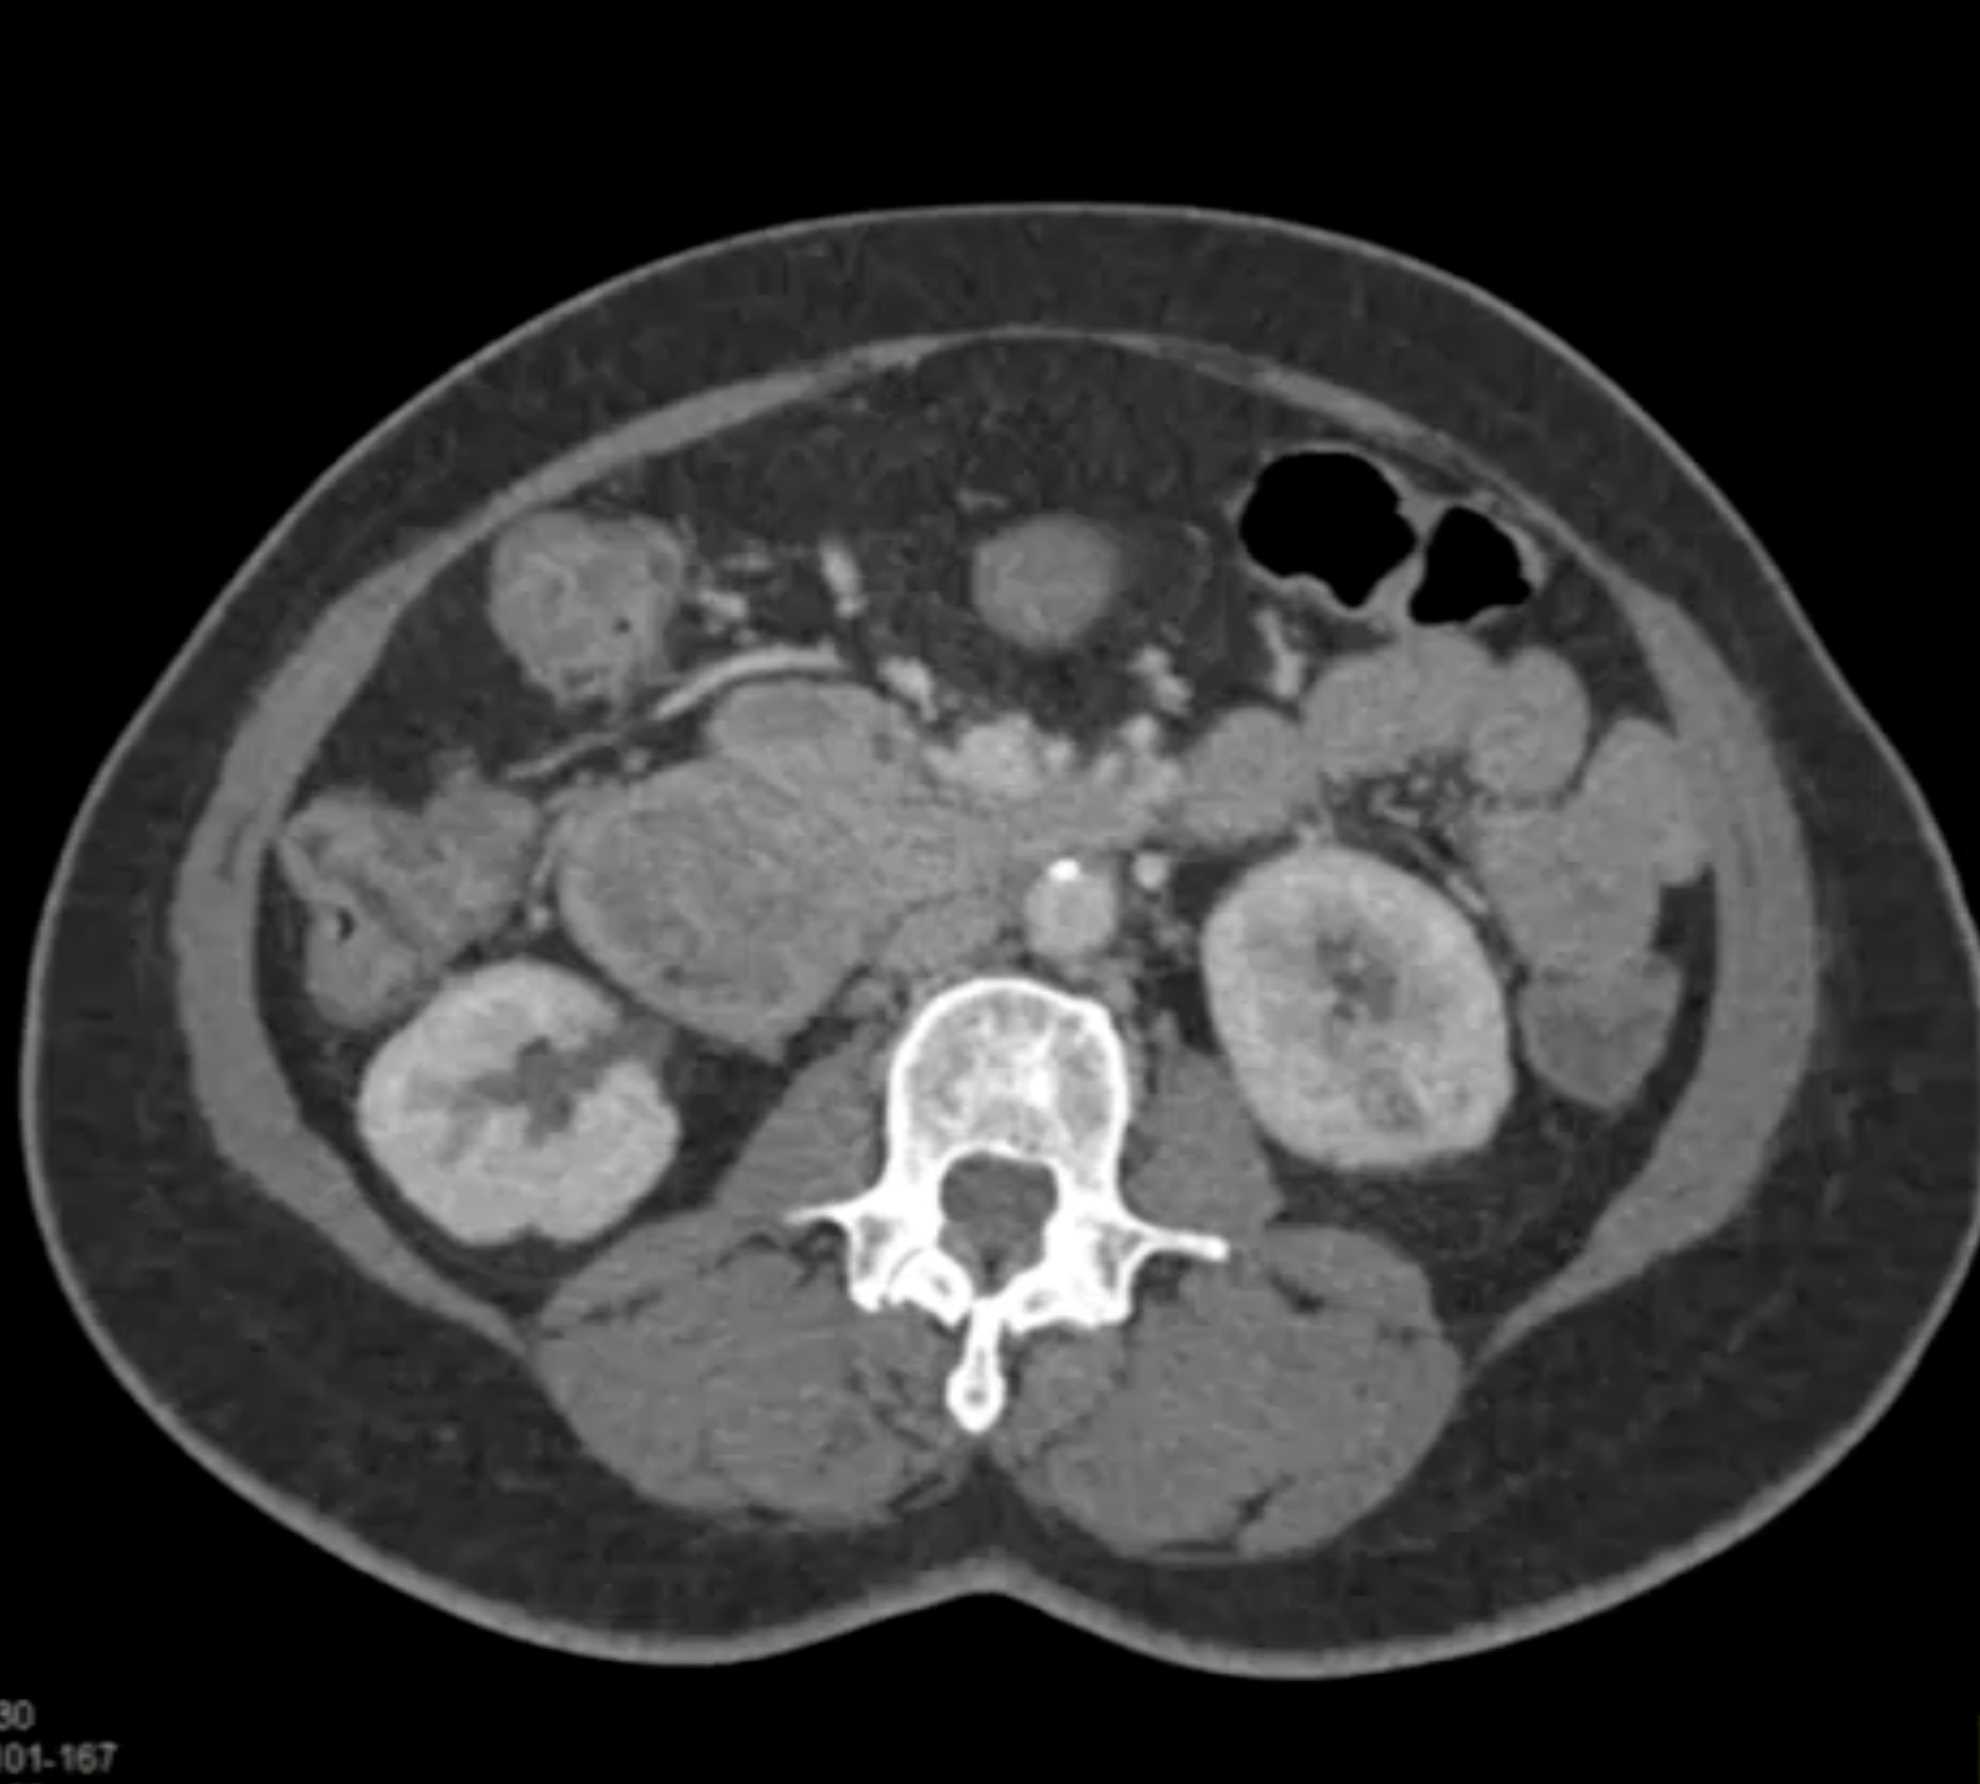

Lagre Gastric GIST Tumor